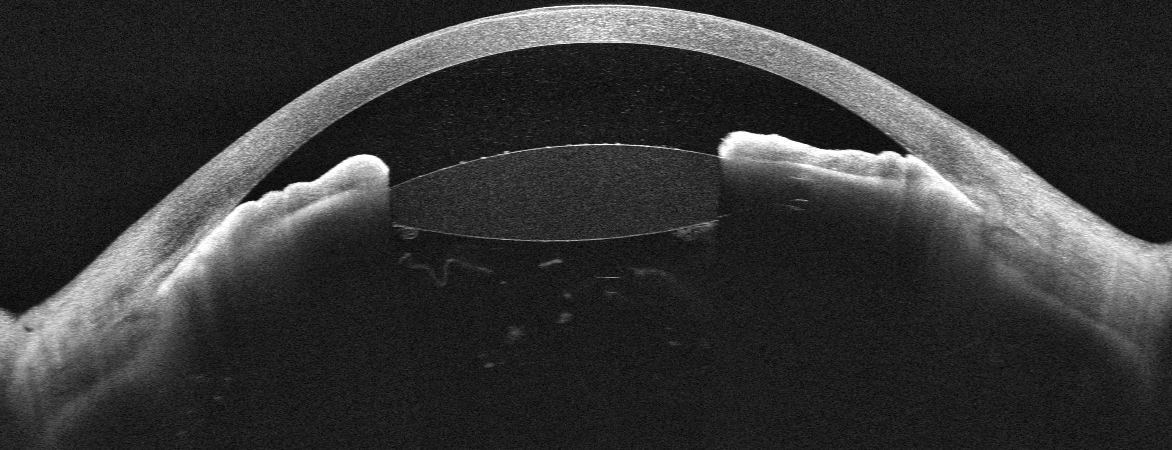

OCT du segment antérieur montrant une fermeture de l'angle avec chambre antérieure plate — glaucome malin

OCT Intalight du segment antérieur — Glaucome malin : chambre antérieure plate avec fermeture de l'angle (IPO Paris)